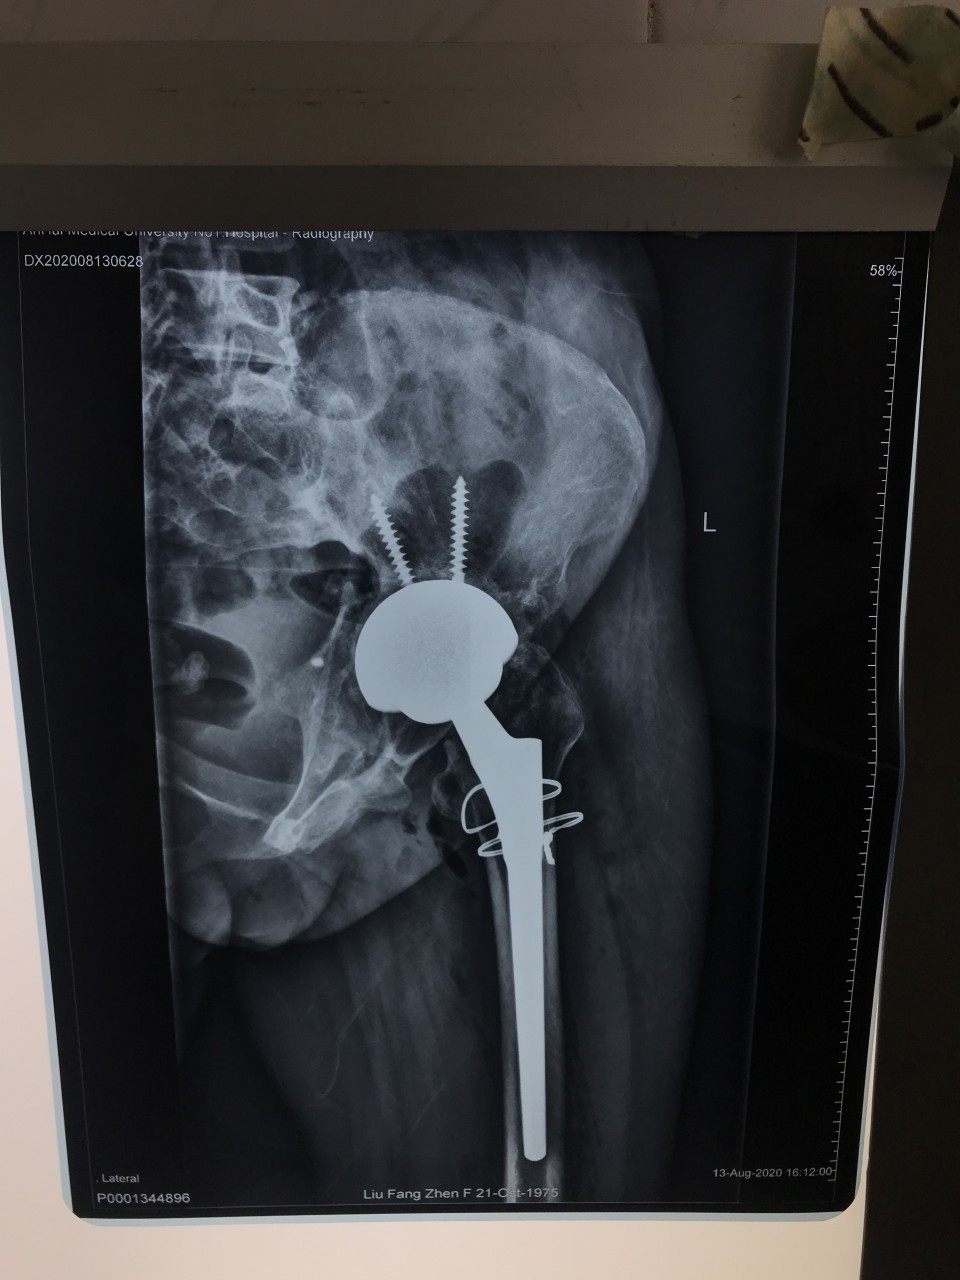

一位44岁女性患者因“左侧骨盆骨折术后疼痛伴渗液8年”入院。患者8年前因左侧骨盆骨折请上海专家行手术治疗,术后恢复不佳,髋关节感染,当地医生将部分钢板取出,残留的钢板因风险极大未予以处理。由于手术不彻底,伤口继续流脓,股骨头坏死,关节疼痛严重。因为手术风险极大,失败率高,多家医院拒收,患者慕名来到我院关节与显微修复外科胡孔足主任专家门诊,胡主任综合考虑各方因素以及现阶段我院的诊疗技术,将患者收治入院予以手术。术前结合患者病史,体检及辅助检查,反复讨论,制定了精细的手术方案,于6月10日,成功行一期手术,取出感染发炎的钢板,植入抗生素占位器。因为钢板和血管神经紧紧粘连在一起,稍有不注意就可能导致大出血,瘫痪、心跳骤停等严重后果。术后培养提示为MRSA,经过两个月规范抗感染治疗,培养提示阴性,未见细菌,感染消失。8月12日,胡主任顺利完成二期手术,“左侧全髋关节置换术”,目前手术后4天,患者已经能够扶拐下地行走,恢复良好,不久将康复出院。